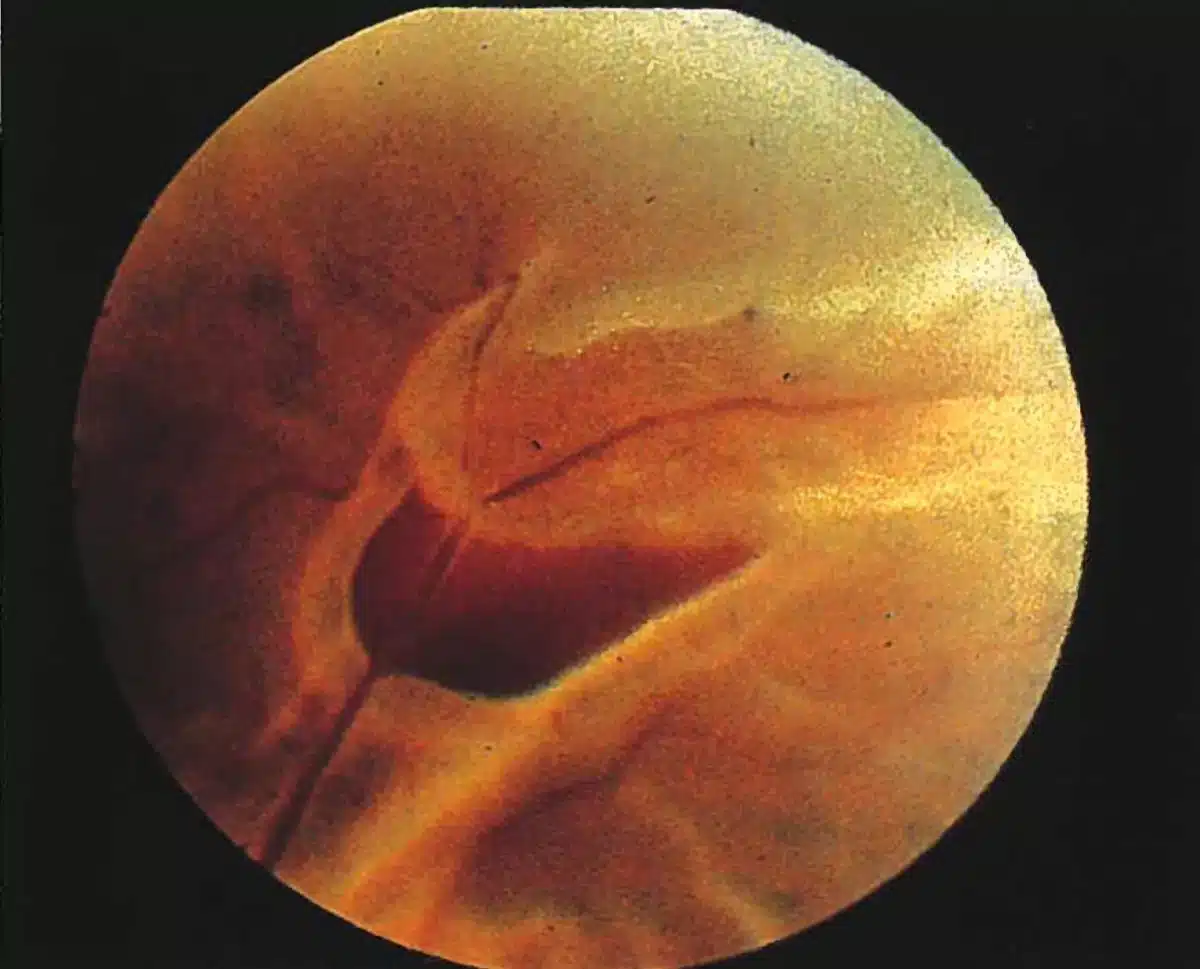

A tear in the retina can be categorized based on its appearance during a clinical exam by an ophthalmologist. There are three main types of retinal tears: an operculated tear (small circle of tissue torn out of the retina), a horseshoe tear (a ‘U’-shaped flap is lifted up), or a Giant Retinal Tear (a tear involving greater than 25% of the retina).

Over time, the vitreous jelly that fills the eye becomes less like jelly and more like water. During this degradation, the vitreous can peel off of the retina and cause tears. Subsequently, the water that fills the eye can go through the tear and under the retina causing a retinal detachment. Referring back to the previous analogy, the eye is like a fluid-filled room with the retina being like the wallpaper in the room. If a tear existed in the wallpaper, fluid could seep underneath it. If enough water got underneath the wallpaper, it would start to peel off and detach. The same is true for the retina. Early recognition of a tear and prompt retinal tear treatment can prevent a large retinal detachment requiring invasive surgical repair.